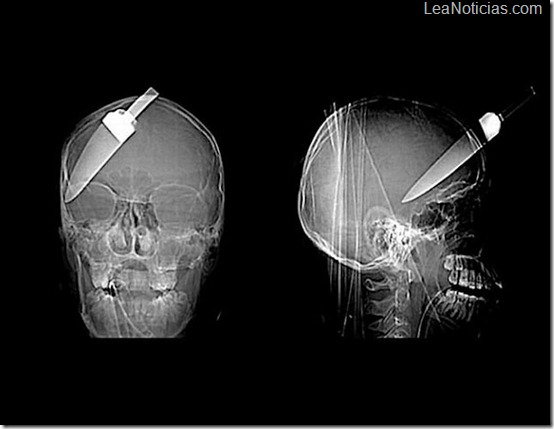

Un clavo en el cráneo de un hombre, el paciente se disparó accidentalmente con un martillo automático. No se había dado cuenta de que el mismo lo disparo y un clavo de 10 pulgadas se encontraba ahí desde hacía 6 días.

Un cuchillo en la cabeza de un niño de 10 años de edad. El joven sobrevivió.

Un cuchillo de 12 pulgadas en el cráneo de un adolescente.

Un cuchillo de embarrar atravesó el cráneo de este paciente por el ojo.